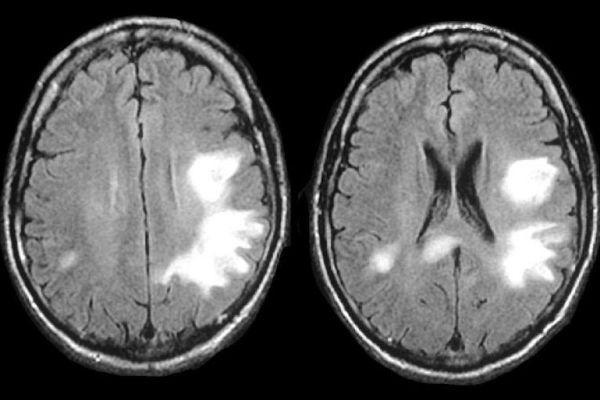

В ходе исследования МРТ обнаруживаются крупные субкортикальные (подкорковые) очаги – гиперинтенсивные (режим Т2) и гипоинтенсивные (режим Т1).

Исследование КТ показывает двухсторонний лейкоареоз – малую ишемию сосудов, повреждения элементов сосудистой системы белого вещества. При перивентрикулярной лейкоэнцефалопатии на МР-томограмме различается диффузно-очаговое поражение белого вещества преимущественно симметричное.

Для сравнения при вирусном поражении очаги расположены преимущественно ассиметрично. Единичный неспецифический очаг лейкоэнцефалопатии может быть ошибочно расценен, как проявление инсульта.

На МРТ обнаруживаются очаги повышенной интенсивности, располагающиеся асимметрично в области белого вещества лобных и затылочных долей. МР картина перивентрикулярной мелкоочаговой лейкоэнцефалопатии: на Т1 режиме очаги низкой интенсивности. Очаги также обнаруживаются в коре головного мозга, стволовых отделах и мозжечке.